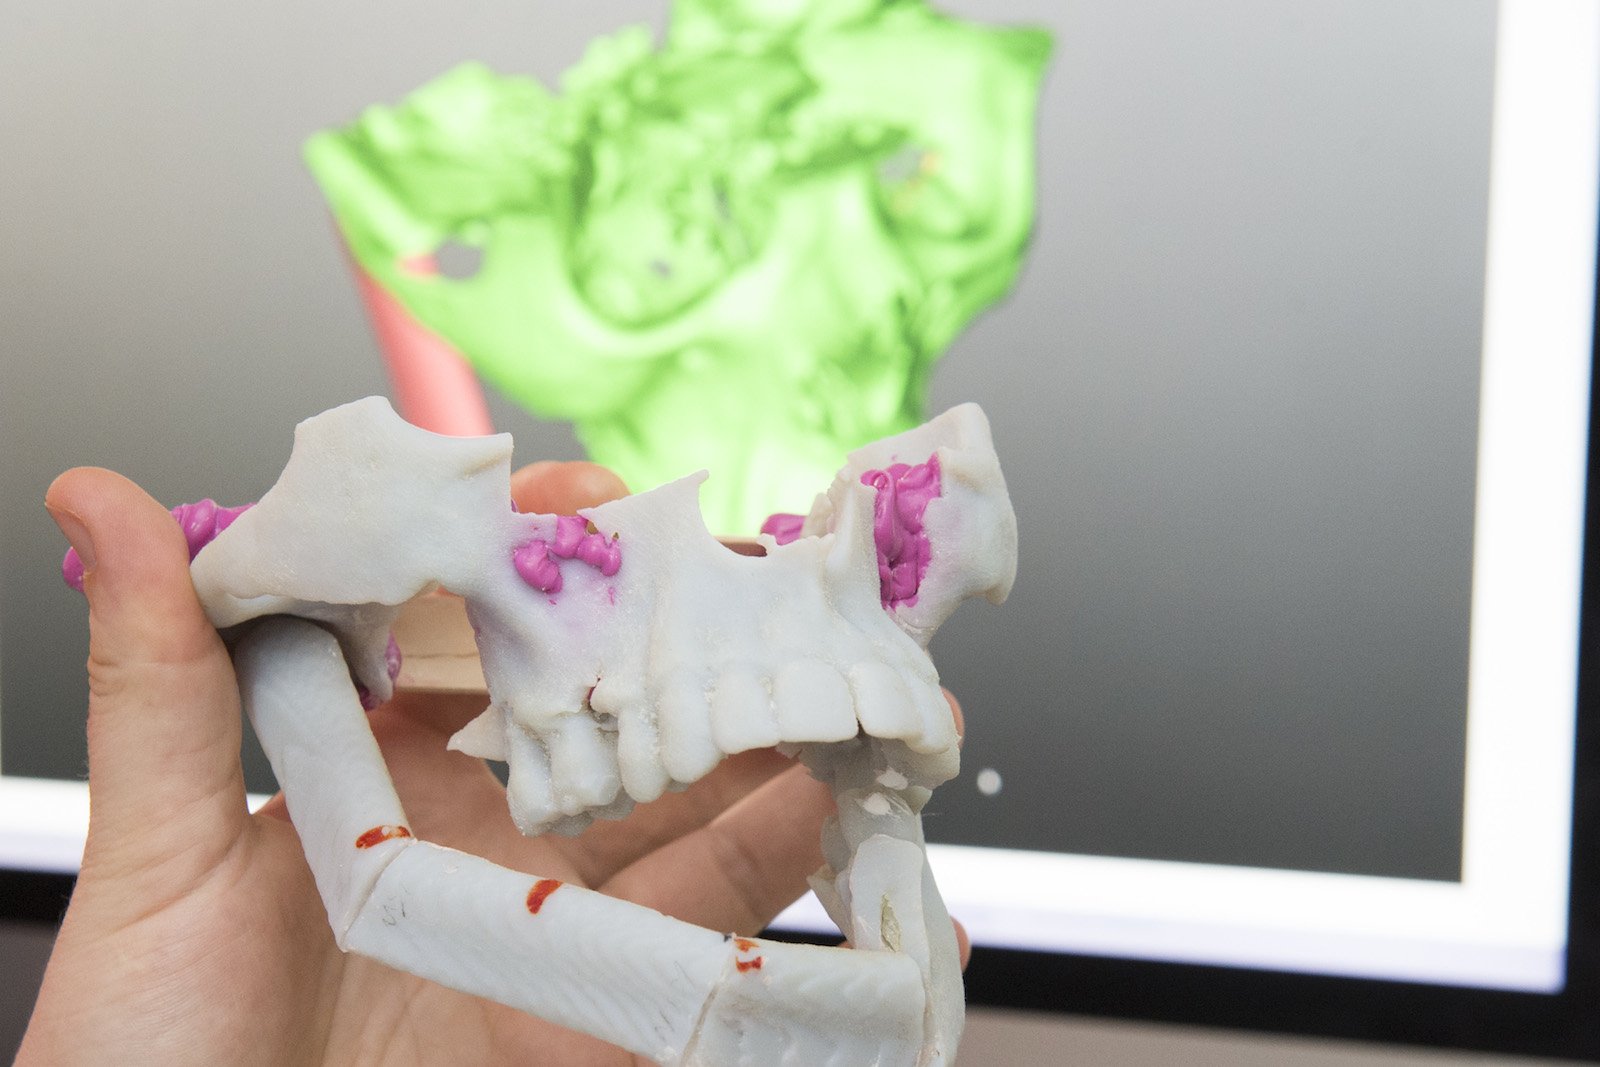

In der Klinik für Mund-, Kiefer- und Gesichtschirurgie (MKG) der Universitätsmedizin Mainz entstehen individuelle dreidimensionale Patientenmodelle aus dem eigenen 3D-Drucker, die selbst kleinste anatomische Strukturen wie fein verästeltes Knochengewebe abbilden. Anhand dieser Modelle können die Mediziner beispielsweise durch Tumorleiden bedingte Kiefer-, Kopf- oder Gesichtsrekonstruktionen operativ besser planen und Transplantate präziser anpassen.

Sei es Nase oder Stirn – der neue 3D-Drucker der Klinik für Mund-, Kiefer- und Gesichtschirurgie (MKG) an der Johannes Gutenberg-Universität kann alles exakt nachbilden. Selbst kleinste Details wie fein verästeltes Knochengewebe bekommt diese Technik hin. Mit solchen maßgetreuen Schablonen können Chirurgen Patienten körpereigene Transplantate passgerechter einsetzen. In Mainz sieht man das als enormen Schritt hin zu einer immer stärker individualisierten Medizin. Die dreidimensionalen Modelle werden im Maßstab 1:1 gefertigt. Die Vorab-Informationen dazu liefern Bildgebungsverfahren wie Computertomographie, Röntgen oder MRT.

Das 3D-Verfahren hat etliche Vorteile: Anhand der Modelle können Mediziner eine bevorstehende Operation gedanklich durchspielen, bevor es ernst wird. Um es zu verdeutlichen: Eine Lücke im Kiefer muss geschlossen werden, dafür soll ein Stück des Wadenbeins entfernt und anschließend an anderer Stelle wieder eingesetzt werden. Zuerst erstellt der 3D-Drucker ein Modell des Kiefers und des Wadenbeins.

Dank der 3D-Modelle kennen die Operateure ihr Operationsfeld bereits und können optimiert planen und anhand der vorgefertigten Schablonen quasi originalgetreu arbeiten. Dadurch reduziert sich die Operations- und Narkosezeit für den Patienten, seine Genesung beschleunigt sich und Funktion sowie Ästhetik verbessern sich. Zudem schont das Verfahren Knochensubstanz, umliegendes Gewebe und Zahnfleisch.

Der Mediziner plant dann die OP am lebensechten Modell und probt sie sogar in Grundzügen. Derart vorbereitet kann er bei der realen OP das Knochenstück aus dem Wadenbein so präzise herausnehmen, dass es passt punktgenau in den defekten hineinpasst. Das ist eine schonende Methode, die weniger Folgeschäden für das Wadenbein hat als eine herkömmliche OP.

Die Mainzer Mediziner haben außerdem beobachtet, dass die transplantierte Stelle besser funktioniert als bei herkömmlichen Verfahren. Zudem sei das ästhetische Ergebnis besser. Außerdem schone das Verfahren die Knochensubstanz, umliegendes Gewebe und das Zahnfleisch, betonen sie. Für Patienten verkürzt sich die OP-Zeit und damit die belastende Narkose. Auch die Genesung wird beschleunigt.